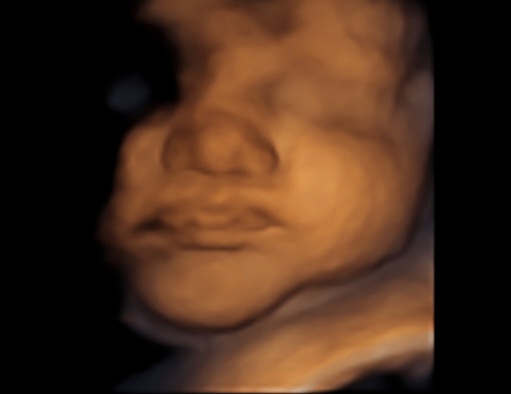

Ещё сегодня ходили на заключительное 3д узи. Такой красивый детеныш у нас получился все таки☺

В конце, по традиции, скорчил очень смешную рожу, мы с мужем и врачом так смеялись, а я до сих пор без смеха не могу смотреть, думаю даже распечатать это фото😂